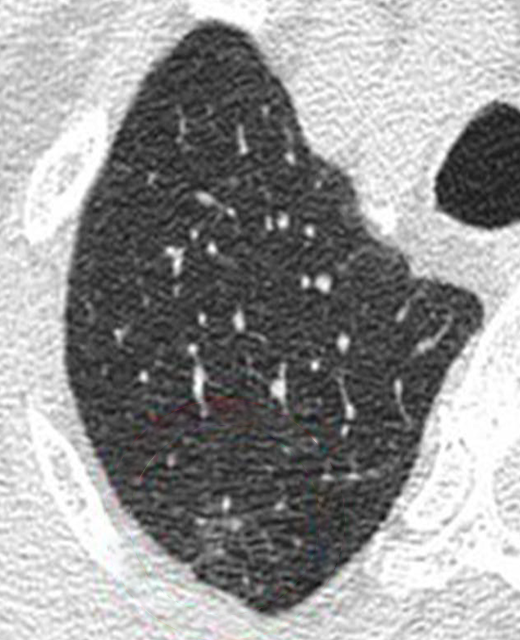

AI technology makes the screening process safer by allowing us to use ultra-low doses of radiation. Sharper images have previously only been possible with larger doses of radiation.

Our AI technology processes the low-dose scan and compares them to similar scans in Fujifilm’s vast library of imaging data. This enables us to sharpen the low-dose image and identify problems that would be missed by the naked eye.

Ultra Low-Dose Scan

A regular scan at ultra-low dose radiation is noisy and unclear, making it possible to overlook a problem.

High-Dose Scan

The same scan with a higher dose of radiation reveals an abnormality.

AI Enhanced Ultra Low-Dose Scan

Our AI technology is able to sharpen the quality of the ultra-low dose scan to assist the doctor in early detection.

FCT PixelShine is our Deep Learning based image processing software that improves the image quality of low-dose radiation scans. Sharper images have previously only been possible with high doses of radiation. FCT PixelShine enables our machines to produce a sharp, clear image even at ultra-low dose radiation.